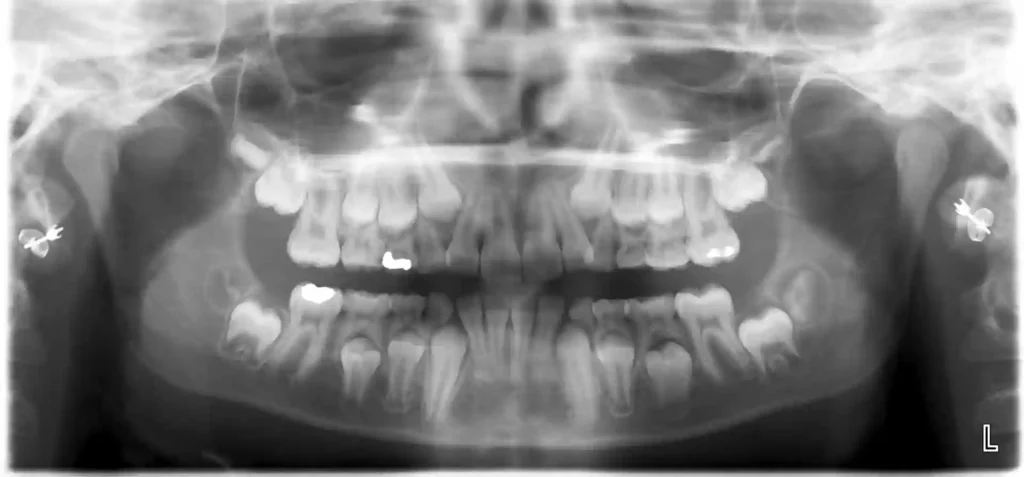

مراحل درمان در کلینیک

معاینه اولیه

↓

رادیوگرافی

تشخیص

درمان مناسب

پیگیری

- رادیوگرافی دیجیتال